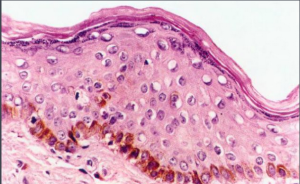

黑素細胞是一種產生黑色素的細胞,負責給頭髮和皮膚提供深顏色。黑色素在體內有多方面作用,並且所有人的身體都有這些細胞。不過,頭髮和皮膚著色不是由黑素細胞的擁有量決定,而是取決於這些細胞的活性。例如,患白化病等疾病的人,雖然存在這些細胞,但它們的活性被抑制住,因此不能產生色素。

除了皮膚以外,大腦,內耳,心臟和眼睛,以及其它身體部位也有黑素細胞。它們通常隱藏在表面下。這些細胞對環境做出反應(如紫外線輻射和某些化學反應),並產生黑色素。這些黑色素游離出黑素細胞,浮到所在位置的組織表面。一段時間後,它分解並被下層黑素細胞新產生的黑色素替代。

黑素細胞 對皮膚來說,黑色素有保護作用。這些色素吸收紫外線輻射,防止它到達身體周圍組織。其結果是,在經常接觸陽光或陽光強烈地區生活的人體內有更多活性黑素細胞。這些細胞讓身體有健康的黑色素層,以減少曬傷或陽光紫外線損傷的風險。